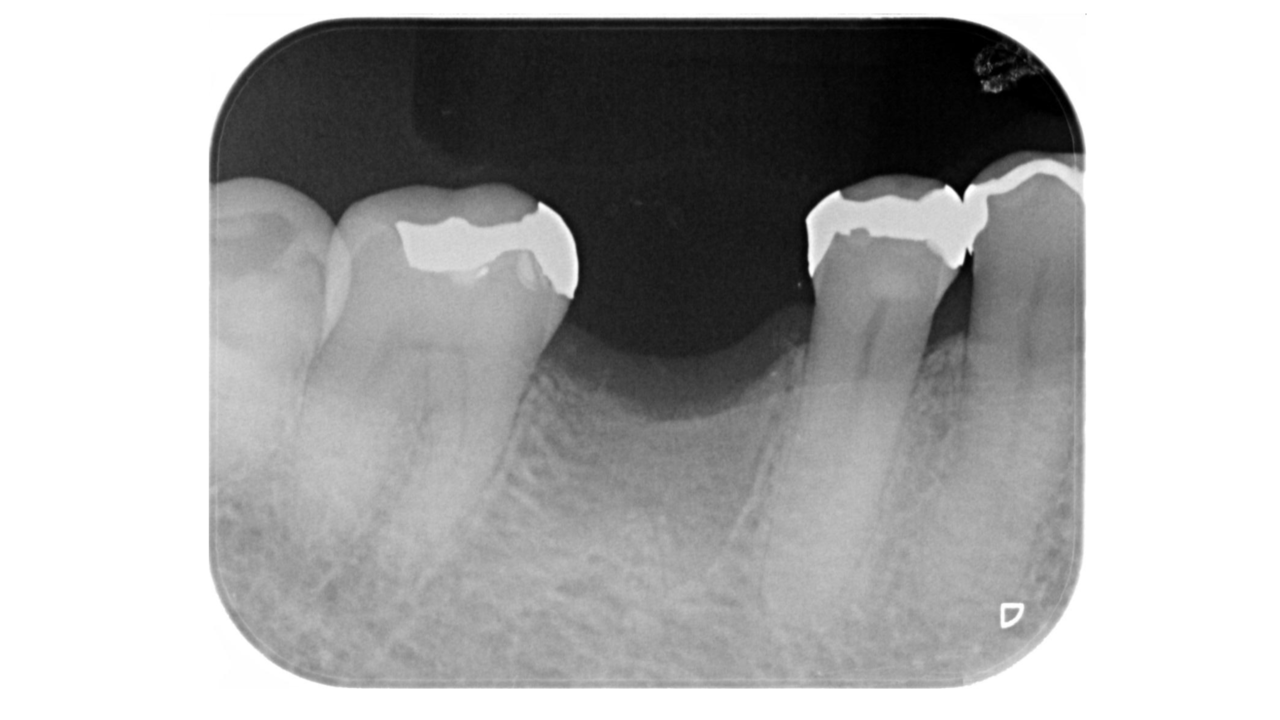

Y・F様 女性 70代

Before

After

以前から左下奥歯がなく硬いものが噛めず、かみ合わせが不安定なため、欠損部にインプラント治療を希望され、治療を開始。治療後、奥歯でしっかり噛めるようになり、食事も美味しく食べれるようになったと満足されていました。

治療期間・回数:7か月、10回

治療の価格:インプラント治療  550,000円 (上部構造含む)

治療のリスクや副作用:手術後に、痛みや腫れ、出血、合併症などを引き起こす可能性があります。噛む感覚がご自身の歯と異なる場合があります。見た目がご自身の歯と異なる場合があります。手術後にメインテナンスを継続しないと、インプラントが脱落するリスクがあります。